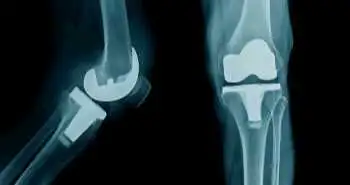

Обережне використання опіоїдів як спосіб профілактики серйозних ускладнень після тотального ендопротезування суглобів

Згідно з результатами дослідження, опублікованими в журналі The Journal of Bone and Joint Surgery, у пацієнтів з високим рівнем споживання опіоїдів у початковій післяопераційній фазі після тотального ендопротезування тазостегнового та колінного суглоба спостерігався підвищений дозозалежний ризик розвитку перипротезної інфекції та венозних тромбоемболічних ускладнень.

Brian C Chung та співавт. досліджували можливий зв'язок між дозою опіоїдів, що застосовуються для усунення болю, та розвитком післяопераційних ускладнень після первинного тотального ендопротезування тазостегнового суглоба (ТЕТС) та тотального ендопротезування колінного суглоба (ТЕКС). До дослідження були включені дорослі пацієнти (n = 1525985, середній вік 65,7 ± 10,8 року, 39,2% - чоловіки, 77% - представники європеоїдної раси), яким провели первинне елективне ТЕТС або ТЕКС в період з 2004 по 2014 р. з реєстрацією прийому опіоїдів (міліграм-еквівалент морфію (MME)) у перші три післяопераційні дні.

Пацієнти були розподілені за квінтилями з урахуванням впливу препарату, вираженого в MME: менше 54, від 54 до 82, від 83 до 116, від 117 до 172 і більше 172 MME. Основні кінцеві точки включали післяопераційну перипротезну інфекцію, емболію легеневих судин, тромбоз глибоких вен та легеневі ускладнення. З метою вивчення відмінностей між групами та визначення інших факторів, які можуть впливати на результат, було проведено одновимірний та багатовимірний аналізи.

Підвищення впливу препарату, вираженого в MME, пов'язували з підвищеною ймовірністю дозозалежного розвитку ускладнень після хірургічного втручання. У пацієнтів, які отримали більше 172 MME, ризик розвитку вищезазначених небажаних явищ (основні кінцеві точки) був вищим, ніж у пацієнтів, які отримали менше 54 MME. Крім того, у пацієнтів, які отримали більше 172 MME, була вищою частота випадків ранових інфекцій та розходження країв рани, а також повторної госпіталізації протягом 30 та 90 днів.

Таким чином, застосування опіоїдів у ранньому післяопераційному періоді із дозозалежним ефектом було пов'язане з розвитком перипротезних інфекцій суглобів та інших ускладнень після ендопротезування суглобів.